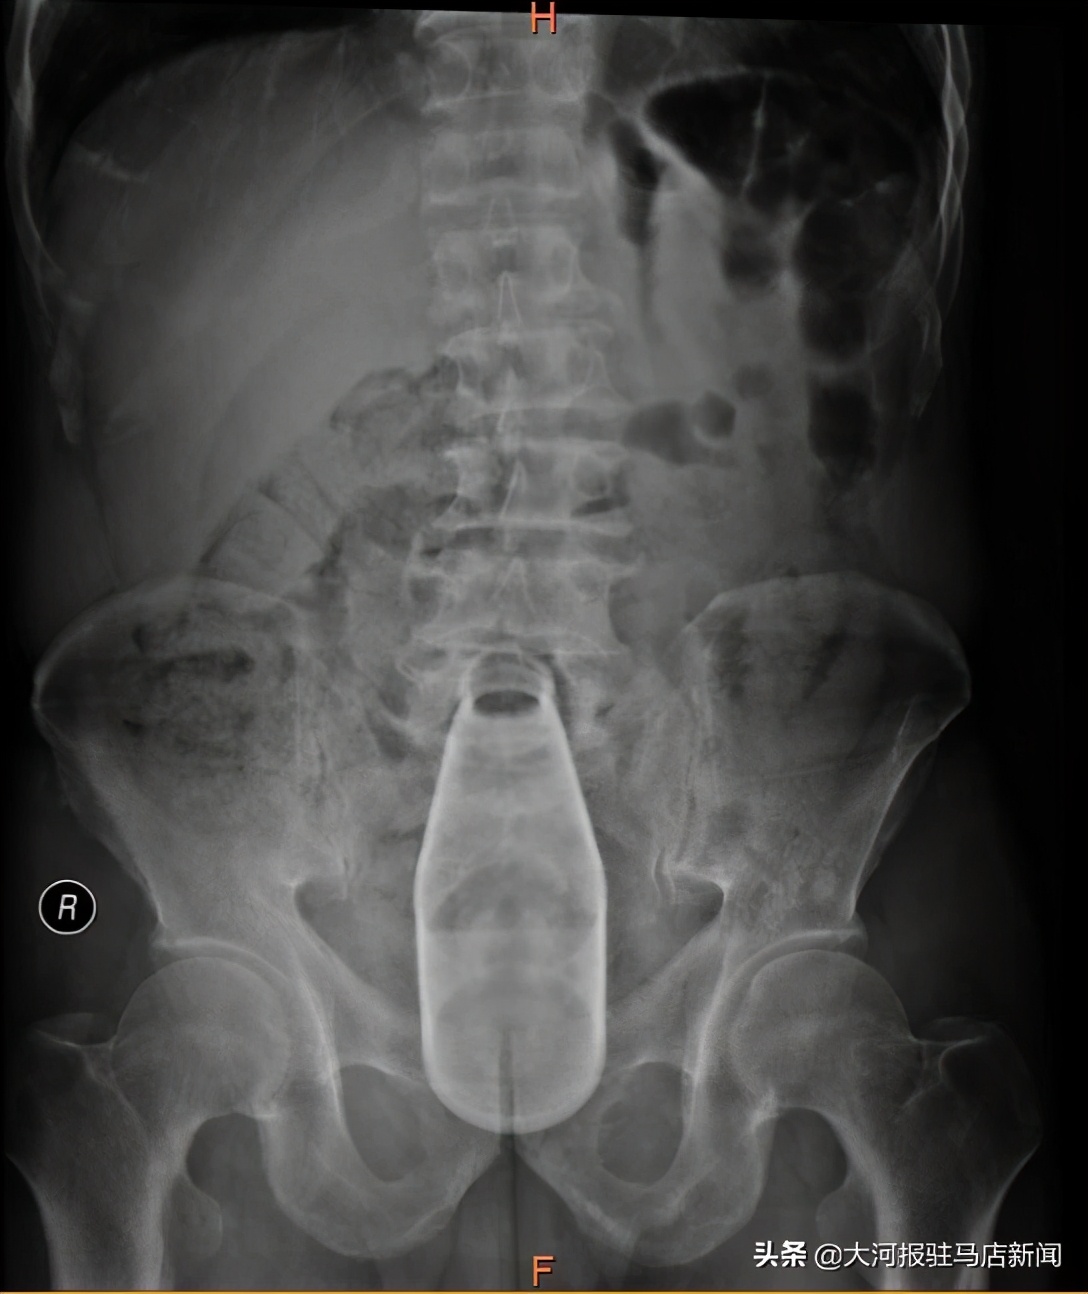

近日,家住驻马店市平舆县的老毕不慎将一个24cm×6cm大小的玻璃瓶塞入肛门,在家中苦苦努力一夜,不但没把玻璃瓶取出,反而导致玻璃瓶越陷越深的情况下,老毕被家人送往驻马店市中心医院肛肠科。

老毕来到医院的时候,已经出现机械性肠梗阻症状,情况十分危急。驻马店市中心医院肛肠科主任代建德立即进行专科查体,发现老毕的肛门不仅出现了明显水肿,更可怕的是手指已经触摸不到玻璃瓶;这意味着,单从肛门取出玻璃瓶的可能性微乎其微。

在麻醉科手术部的密切配合下,由团队中手尺寸最小的副主任医师于秀芝自肛门探查玻璃瓶的大概位置,发现玻璃瓶位于直肠乙状结肠交界处,代建德在患者腹部轻柔挤压肠管,将玻璃瓶缓慢推向直肠末端。另一组医生王文航通过肛门撑开器将患者的肛门撑开,触摸到玻璃瓶后,用手术器械将其轻柔地向外牵拉,数名医生上下其手,一起发力,历经一个多小将其成功取出,避免了开腹手术,减轻了患者的创伤。术后第二天,老毕的不适症状明显减轻,术后第三天便顺利康复出院。